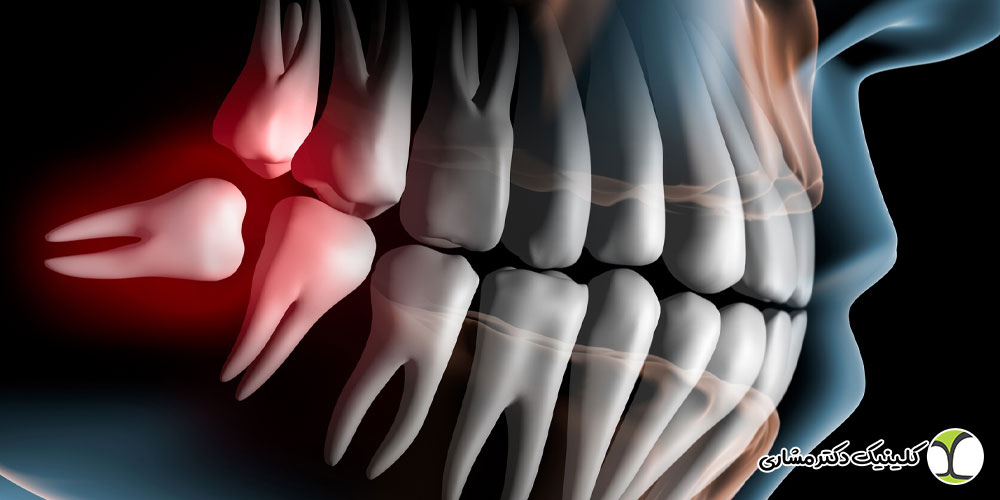

جراحی دندان عقل یکی از رایج ترین روش های دندان پزشکی است که برای برداشتن دندان های عقل انجام می شود. این دندان ها معمولا در سنین نوجوانی یا اوایل بیست سالگی شروع به رشد می کنند، اما گاهی اوقات به درستی رشد نمی کنند و مشکلاتی ایجاد می کنند. دندان های عقل ممکن است باعث درد، عفونت یا آسیب به دندان های دیگر شوند.

- گیر کردن دندان عقل داخل لثه (نهفته یا نیمه نهفته)

- ایجاد فشار روی دندان های دیگر

- آسیب به ریشه دندان های کناری یا استخوان فک

- بررسی اولیه و عکس برداری: پیش از جراحی، دندان پزشک وضعیت دندان عقل را بررسی می کند. معمولا عکس برداری مثل عکس پانورامیک انجام می شود تا مشخص شود که دندان در چه وضعیتی است، آیا نهفته است یا بیرون آمده و آیا به دندان های کناری یا عصب ها نزدیک است یا نه.